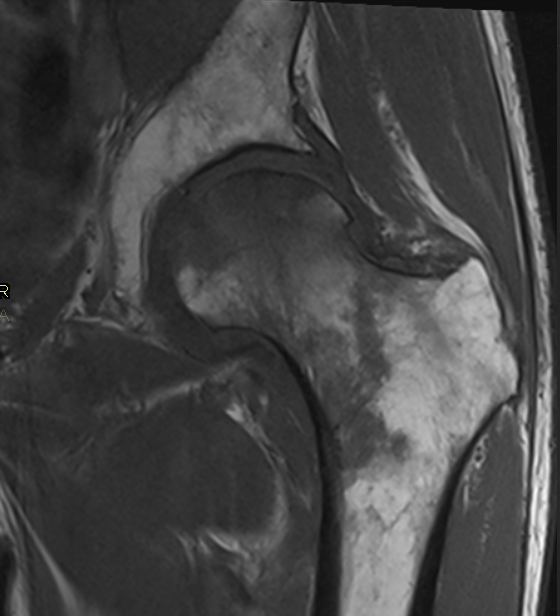

3. Avascular necrosis of femoral head